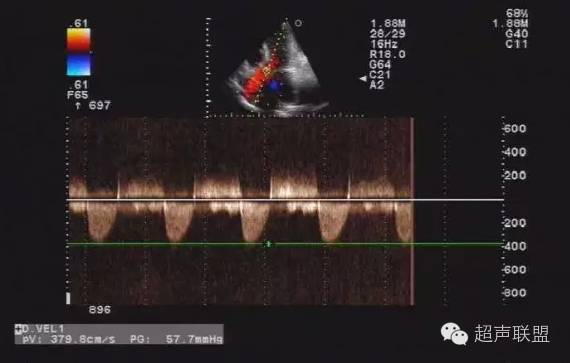

(4)用频谱多普勒连续波多普勒记录收缩期主动脉瓣口射流频谱,测量最大和平均跨瓣压差,在左心室收缩功能减退的患者以连续性方程法估测主动脉瓣瓣口面积。以脉冲波多普勒记录舒张期二尖瓣血流频谱,测量舒张早期E波与心房收缩期A波最大流速的比值。

平均跨瓣压差》25mmHg为轻度狭窄;25~50mmHg为中度狭窄,大于50mmHg为重度狭窄。

正常成人瓣口面积约3.0~4.0cm2,按照狭窄的程度可将主动脉瓣狭窄分为轻度狭窄(瓣口面积≥1.5cm2),中度狭窄(瓣口面积1.0~1.5cm2)和重度狭窄(瓣口面积≤1.0cm2)。也有的根据瓣膜的跨瓣压差进行分级,平均跨瓣压差小于30mmHg为轻度,30~50mmHg为中度,大于50mmHg为重度。

(三)超声心动图检查 M型超声可见主动脉瓣变厚,活动幅度减小,开放幅度小于18mm,瓣叶反射光点增强提示瓣膜钙化。主动脉根部扩张,左心室后壁和室间隔对称性肥厚。二维超声心动图上可见主动脉瓣收缩期呈向心性弯形运动,并能明确先天性瓣膜畸形。多普勒超声显示缓慢而渐减的血流通过主动脉瓣,并可计算最大跨瓣压力阶差。